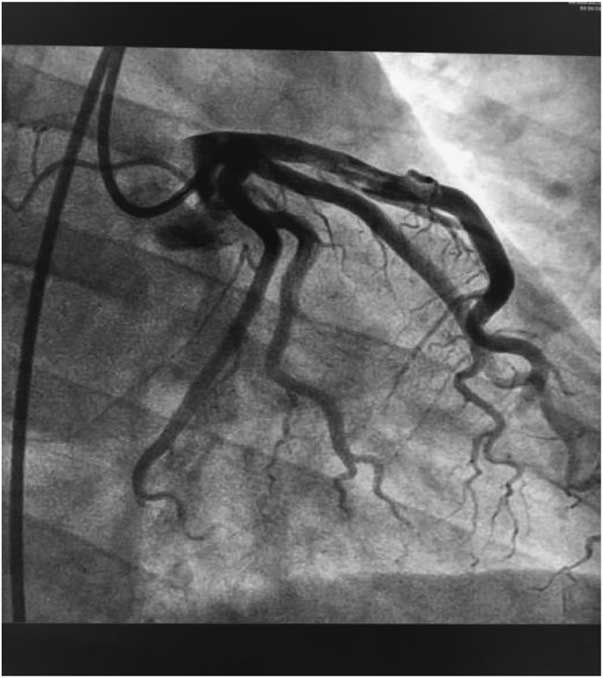

According to the results, our preliminary diagnosis was acute inferior myocardial infarction (Killip grade I) combined with nephrotic syndrome, and we performed a percutaneous intervention procedure, which was followed by 300 mg aspirin and 300 mg clopidogrel orally immediately. During the operation, we saw that the left coronary artery had thickened and the left main artery, left circumflex artery, and right coronary artery were normal. However, there was a great deal of thrombi blocking the anterior and middle anterior descending branch, resulting in 95% stricture (Fig 2) and leading to bloodstream classification at thrombolysis and thrombin inhibition in myocardial infarction grade II. Next, we applied the thrombus suction technique and injected 13 ml of tirofiban to dissolve blood clots. Unfortunately, there was still medium thrombi remaining and 60% stricture in the re-examination of coronary arteriography (Fig 3). The bloodstream classification at thrombolysis and thrombin inhibition in myocardial infarction grade III. Because the anterior descending branch dilatation made it unsuitable for stent implantation, we had to stop further operation. Next, we gave him a therapeutic regimen of low-molecular-weight heparin for 7 days, 100 mg aspirin per day, and 90 mg ticagrelor twice a day to fight platelet aggregation, and 40 mg atorvastatin per night to remedy hyperlipidaemia persistently.

Figure 2 Before the thrombus suction operation.